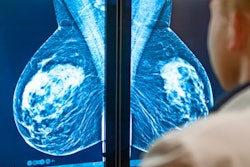

Breast cancer is the leading cause of cancer death among women around the world, Arab Ahmadi noted. Screening for the disease with mammography can be tricky, however: High resolution is needed to identify small lesions, there can be indistinct boundaries on some lesions that mimic normal tissue, and high variation exists among fibroglandular patterns. All of these characteristics can make finding breast cancer with mammography challenging for less experienced readers.

That's how AI can help, Arab Ahmadi said. He and colleagues explored whether an AI algorithm could improve junior radiologists' cancer detection performance via a study that included 2,060 digital mammography exams from 515 women taken between 2018 and 2022. Of these exams, 240 showed malignancies and 1,820 were benign. Four junior radiologists reviewed and interpreted the exams without assistance from the AI algorithm and then were presented with AI-generated interpretations of the same exams and given the opportunity to revise their interpretations. Arab Ahmadi's group compared radiologist performance before and after AI assistance, tracking measures such as the area under the receiver operating curve (AUC), sensitivity, and specificity.